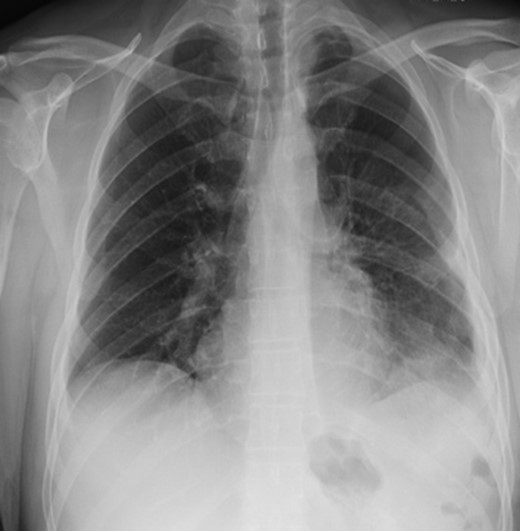

We present a 44-year-old male patient came to the emergency department complaining of right upper quadrant abdominal pain. The patient reported taking over-the-counter (OTC) ibuprofen intermittently for a past few months due to backaches. His past medical history is only positive for falling off a 15 feet ladder at the age of 15 years old. Upon examination, he had right upper quadrant abdominal tenderness, a heart rate of 90 beats/min and a respiratory rate of 20 breaths/min on room air. The patient clinical status was stable and looked well. Chest x-ray showed a moderate left hemidiaphragm elevation with bowel contents overlying the left chest (Fig. 1). Of note, a large amount of air inferior to the right hemidiaphragm was indicative for pneumoperitoneum. Laboratory investigations were immediately carried out and revealed a white blood cell count (WBC) of 4.5 × 109/L (normal range: 4–11 × 109/L). The WBC remained at the normal level until the end of the patient’s admission. Further imaging studies were ordered due to the peculiar coexistence of x-ray findings and stable clinical status. The computed tomography (CT) scan showed a contracted left lung with severe volume loss and just mild aeration of the left upper lung (Fig. 2). No definite left pneumothorax was seen. The majority of the left hemithorax was filled with abdominal contents including the stomach, spleen, pancreatic tail, left kidney, splenic flexure of the colon, and small bowel loops. A small hypodense focus was observed within the intra-thoracic stomach and extended to the stomach wall, with mild adjacent stranding of fat and a small amount of free fluid. We suspected the presence of perforated gastric ulcer secondary to non-steroidal anti-inflammatory drugs (NSAIDs) usage. The upper gastrointestinal (GI) series was performed and did not show any extravasation, indicating that there was some other source or the gastric perforation had walled off. The patient was thus managed conservatively; his diet was advanced and the patient discharged home on Day 4.

CT scan showing collapse of left lung and left diaphragmatic hernia.